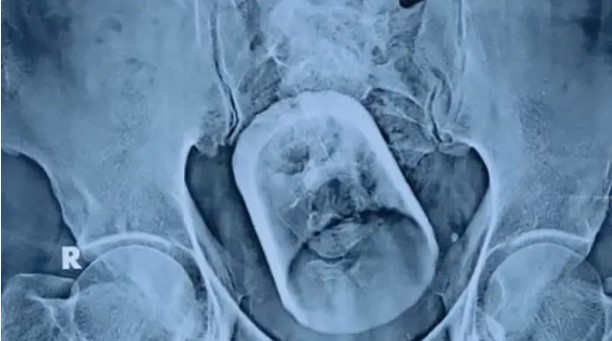

居住在比哈爾邦的55歲男子,近日因為腹痛、便祕而到醫院求診,醫生先替他進行超音波和X光片檢查,未料竟在他的腹部發現一個中等大小、呈圓柱體的異物,仔細觀察後才驚覺,造成男子肚子不舒服的罪魁禍首,竟是一個「玻璃杯」。

一開始醫生試圖透過內視鏡手術將玻璃杯取出,但杯子實在太大,又是玻璃材質,一不小心就可能使它在體內破裂,因此這個方案以失敗告吹,最終不得不選擇剖腹手術,才順利把玻璃杯從男子的體內移出。